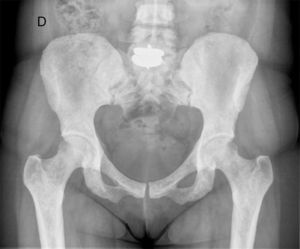

En un control radiográfico rutinario de la columna lumbar (fig. 1), se observan numerosos focos pequeños, bien definidos, homogéneos, circulares, de mayor densidad ósea, en los cuerpos vertebrales, a lo largo de todo el esqueleto axial, por lo que se amplía estudio con radiografía de pelvis AP (fig. 2) y TAC de pelvis y cuerpo vertebral lumbar (figs. 3 y 4), que mostraban lesiones radiodensas redondeadas u ovales en la cabeza y el cuello femorales y en regiones pertrocantéreas, con presencia de pequeñas áreas de densidad aumentada en la pelvis y en los cuerpos vertebrales que indicaban como primer diagnóstico osteopoiquilia. No se observaban componente de partes blandas, ni áreas de rotura de la cortical, ni presencia de reacciones periósticas de características agresivas.